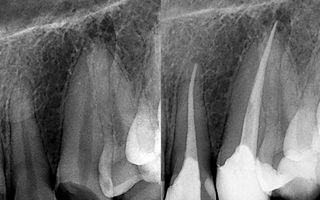

What is a root canal?

A root canal is the name of a treatment that repairs the damaged soft tissue inside a tooth. This soft tissue is known as the dental pulp, and is composed of connective tissue, nerves, and blood vessels. Together, this tissue helps the tooth to grow.

This treatment will remove the damaged pulp and replace it with dental filling. The good news is that the pulp is no longer necessary in adult teeth because it has already completed its task of helping that tooth to grow, however the filling will replace the pulp to retain the strength and health of the tooth.